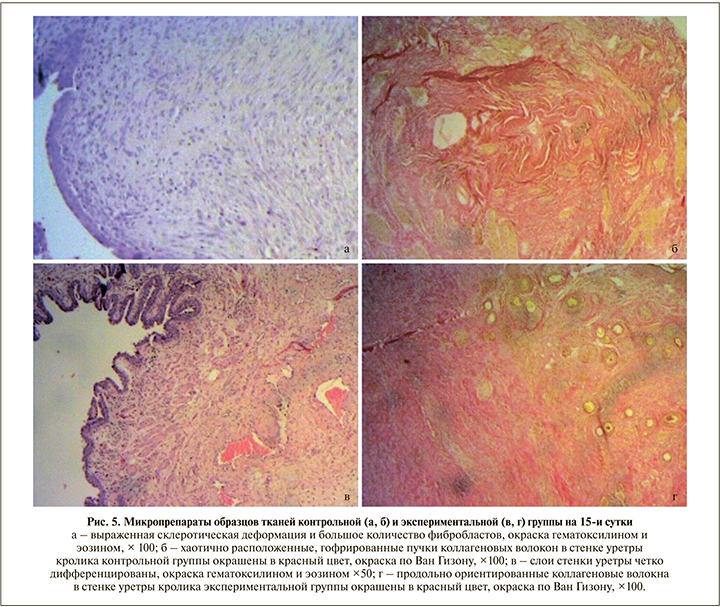

При изучении микропрепаратов контрольной группы, полученных на 15-е сутки после операции (рис. 5, а), зон некроза на всем протяжении стенки не обнаружено. Уротелий, покрывавший слизистую оболочку уретры, несколько уплощен. Собственная мышечная пластинка не прослеживалась, сливалась с подслизистой основой. В подслизистом слое имели место хаотично расположенные коллагеновые волокна с большим количеством фиброцитов и фибробластов. Мышечные волокна с вытянутыми ядрами с заметными ядрышками, межклеточные границы нечеткие.

В экспериментальной группе на 15-е сутки (рис. 5, в) ни в одном из представленных слоев стенки уретры некротических изменений не выявлено. Слои стенки уретры хорошо дифференцированы. Слизистая оболочка, представленная 6–8 слоями эпителиальных клеток, формировала множественные складки. Собственная мышечная пластинка слизистой оболочки гипертрофирована, прослеживалась на всем протяжении. Подслизистый слой с незначительным отеком. В области шовного материала замечена гистиоцитарно-макрофагальная воспалительная инфильтрация. Мышечный слой (прослеживался на отдельных участках) представлен гладкомышечными клетками удлиненной веретеновидной формы, в которых хорошо определялась центральная часть, содержавшая палочковидное ядро, и заостренные концы клеток, проникавшие в промежутки между соседними клетками. В части клеток было видно центрально расположенное ядро, имевшее округлый вид на поперечном срезе. Между миоцитами визуализировались тонкие прослойки рыхлой соединительной ткани. Краткое описание морфологических изменений представлено в табл. 1.

При окраске по Ван Гизону и при анализе данных, полученных при иммуногистохимическом исследовании, значимых различий в экспрессии коллагена между группами на 3-и и 7-е сутки выявлено не было. Однако на 15-е сутки в образцах контрольной группы (по сравнению с экспериментальной) отмечена избыточная продукция коллагена с субтотальным замещением всех структурных элементов, а также хаотичное расположение коллагеновых волокон в стенке уретры, что может свидетельствовать о выраженной синтетической активности фибробластов с последующей коллагенизацией стромы в рамках компенсаторно-приспособительных реакций (рис. 5 б, г).